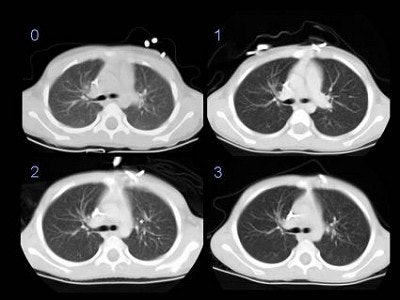

The MGH group reduced the mAs in incremental stages. In phase 0: kVp 120, mAs 210, pitch 1.0, slice thickness 5, calculated CTDIw 25. In phase 1: kVp 140, mAs 140, pitch 1.5, slice thickness 7, calculated CTDIw 23. In phase 2: kVp 140, mAs 130, pitch 1.5, slice thickness 5, calculated CTDIw 19. In phase 3: kVp 140, mAs 80, pitch 1.5, slice thickness 5, calculated CTDIw 12. Images courtesy of Dr. Hamid Salamipour.![]() |